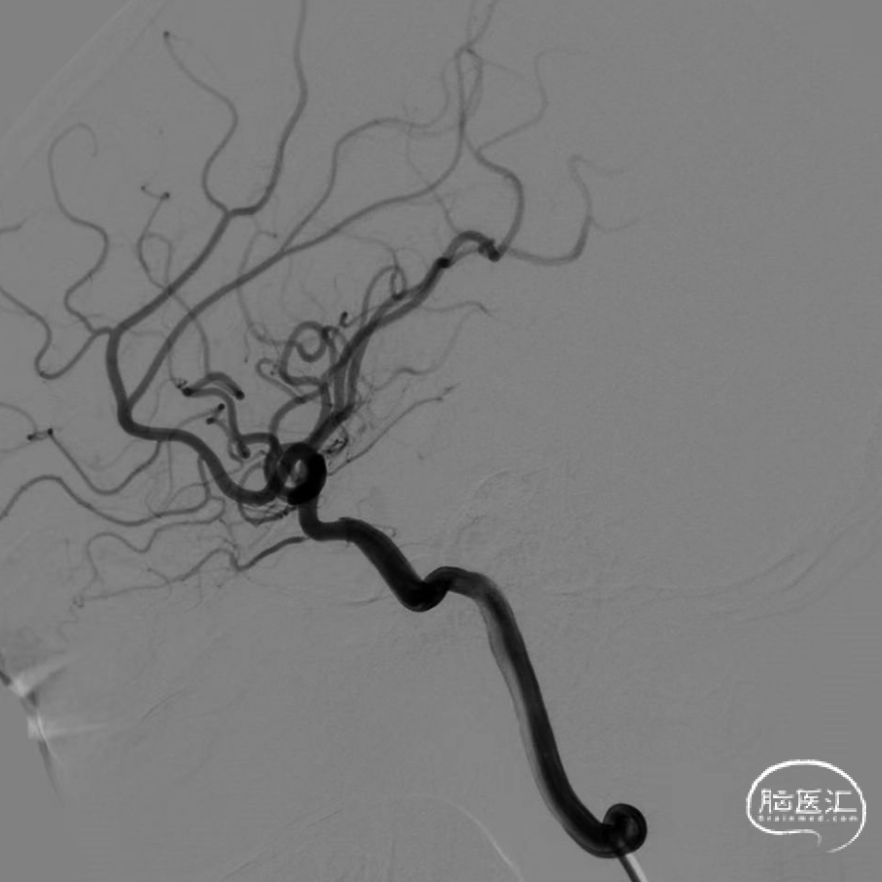

术中DSA造影:左侧颈内动脉正、侧位及3D造影,显示左侧颈内动脉海绵窦段动脉瘤,左侧后交通动脉起始端壶腹膨大。

术中DSA造影:左侧颈内动脉3D造影,显示左侧颈内动脉海绵窦段动脉瘤,载瘤动脉远端直径3.36mm;近端直径4.20mm。

完全释放FRED 4017血流导向密网支架,正、侧位及3D造影观察,载瘤动脉通畅、后交通动脉开放、支架贴壁良好、动脉瘤内造影剂滞留。

术后3个月DSA随访,左侧颈内动脉正侧位造影,可见瘤颈缺损处内皮化,动脉瘤完全不显影,后交通动脉畅通。